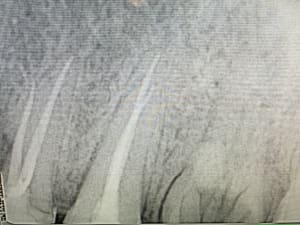

03_gazette_3-14_FM_Müller_Implants_dentaires_gavk9q.pdf